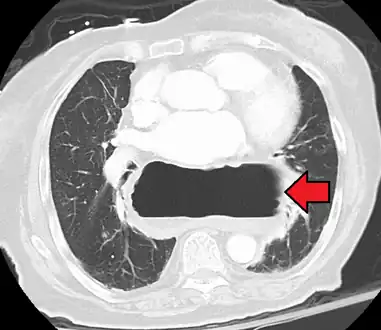

A large hiatal hernia as seen on CT imaging

A large hiatal hernia as seen on CT imaging- As seen on ultrasound[9]